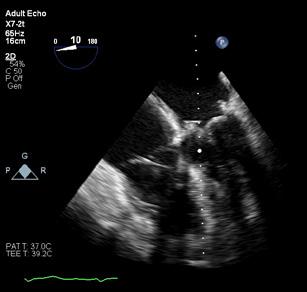

Cazuri disperate în chirurgia cardiacă –atunci când abordul minim invaziv este soluția

Dr. Ion Iovu, Prof. Univ. Dr. Lucian Dorobanțu, Dr. Andreea Bogdan, Dr. Ioana Băjenaru, Dr. Oana Ioniță, Dr. Mădălina Cojocaru, Dr. Toma Iosifescu, Conf. Dr. Cătălin Badiu, Dr. Alexandru Vasilescu